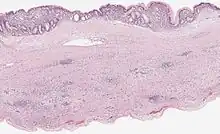

Mucinous cystadenoma of the pancreas 6 |